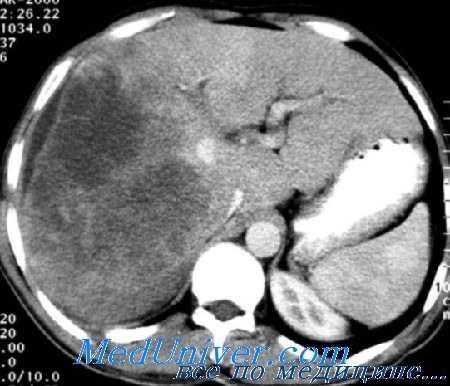

КТ ангиография/портография и КТ сканирование «с отсроченным снятием сканов» после внутриартериального введения Липидола — очень чувствительный и специфический метод диагностики, позволяющий определить даже небольшие очаги поражения. Можно считать, что в настоящее время это метод выбора для диагностики НСС.

Наиболее информативна для данного обследования компьютерная томография . Дополнительный метод обследования — лапароскопия с лапороскопическим УЗИ. Это позволяет выявить больных с нерезектабельным заболеванием (эктрапеченочное распространение, множественное поражение, дополнительные опухоли). Такая стратегия оправдана, поскольку 12% больных (даже при тщательнейшей диагностике) в ходе операции оказываются нерезектабельными.

- КТ и МРТ помогают уточнить локализацию и размер опухоли, а также ее взаимодействие с окружающими тканями (прорастание в кровеносные сосуды печени).

УЗИ органов брюшной полости служит высокоинформативным методом, позволяет обнаружить узловые образования, предположить их злокачественный характер, оценить изменения паренхимы органа. КТ и МРТ печени назначаются врачом-онкологом для детальной визуализации образования с определением размеров, степени распространенности процесса, прорастания опухоли в систему воротной вены, печеночные протоки или соседние органы. Обязательный метод диагностики - пункционная биопсия печени с проведением гистологического исследования тканей и определением типа опухоли и степени дифференциации.